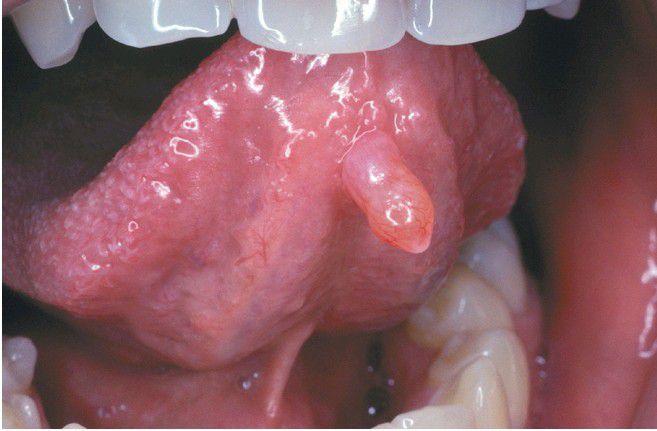

Mucocele

. Exophytic lesion on the anterior ventral tongue.

Ventral